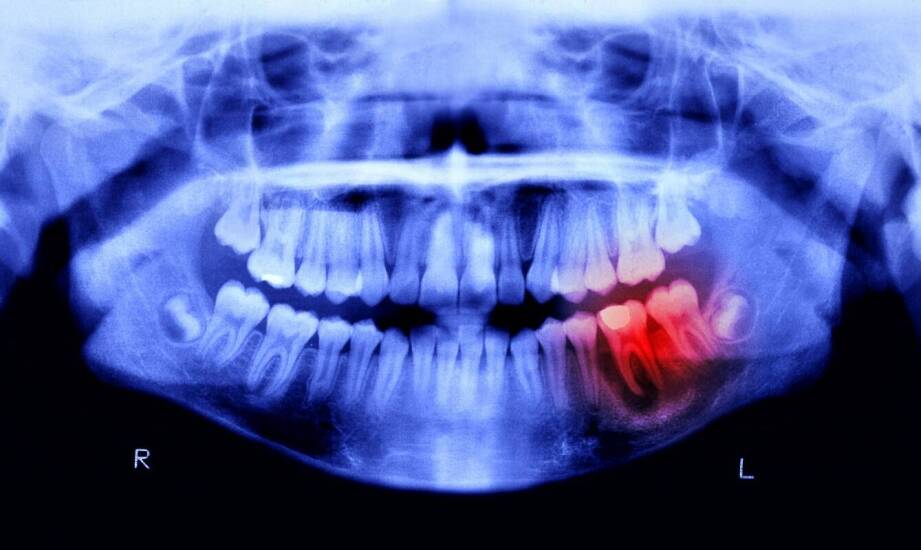

Pantomografia to panoramiczne zdjęcie rentgenowskie, które ukazuje zęby, kości szczęk, zatoki i stawy skroniowo-żuchwowe. Ma na celu wykrycie ukrytej próchnicy, ubytków, torbieli, złamań oraz położenia zębów zatrzymanych. Ocenia strukturę kostną przed implantacją i rozpoznaje patologie zatok. Badanie to jest istotne w kontekście planowania ortodontycznego, chirurgicznego oraz protetycznego.

Pantomogram ujawnia układ zębów oraz obecność zębów zatrzymanych i ich położenie. Wykonany pantomograf w Kaliszu wykrywa ubytki próchnicowe oraz zmiany zapalne. Widoczne są złamania korzeni, resorpcje oraz nieprawidłowości anatomiczne. Ocena gęstości kości jest istotna w kontekście planowania implantów i zabiegów chirurgicznych. Pantomografia obejmuje również wypełnienia, protezy oraz nieprawidłowości stawów skroniowo-żuchwowych.

Pantomogram ocenia kość wyrostków zębodołowych, jej wysokość, szerokość i gęstość oraz zmiany patologiczne. Widoczne są cechy zapalenia kości wokół korzeni. Badanie ukazuje stan zatok szczękowych oraz potencjalne przetoki. Ocena przyzębia przez porównanie poziomu kości względem koron dotyczy wykrywania choroby przyzębia. Pantomogram jest narzędziem, które ma na celu wspomaganie przygotowania do operacji chirurgicznych oraz implantologicznych, identyfikując miejsca z niedoborem tkanki kostnej w gabinecie stomatologicznym 24h Kalisz.